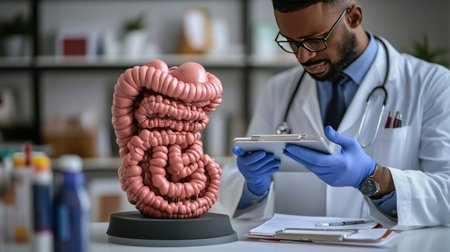

Concept of health care, stomach and intestinal problems

A medical professional in a laboratory setting examines a detailed 3D model of the human intestine, highlighting the importance of education and research in healthcare.

Doctor examines digestive system model and ultrasound image. Stomach intestine ulcers cyst and oncology and examination